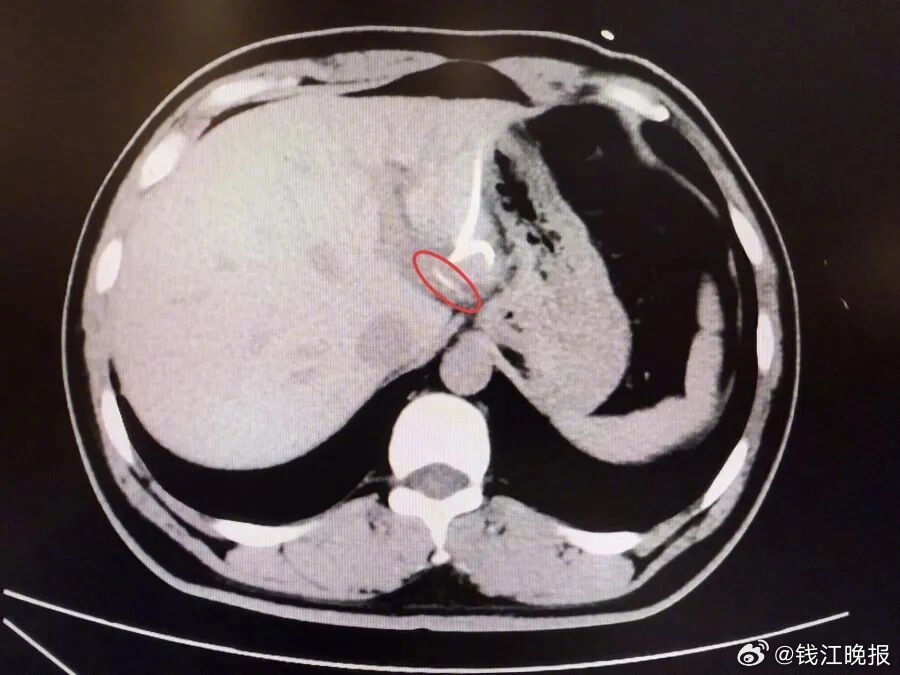

【#男子误吞鱼刺险要切肝保命#】半月前,37岁的李先生(化名)误吞鱼刺却未察觉,数天后出现腹痛、高热(达40℃)等症状,当地医院诊断为“肝脓肿”,治疗后症状反复,CT检查才发现肝脏左叶有鱼刺——其已穿透胃壁入肝引发感染,十分危险,当地医生评估后认为,要彻底清除异物,需要进行左半肝切除手术,这让李先生难以接受。

为寻求更精准、微创的治疗,李先生转至复旦大学附属中山医院内镜中心。“鱼刺位置非常凶险,就在贲门旁刺入左肝,紧贴大血管。”接诊的周平红主任指出,鱼刺位于贲门旁左肝处,紧贴大血管,且腹腔感染粘连严重,手术难度极高。